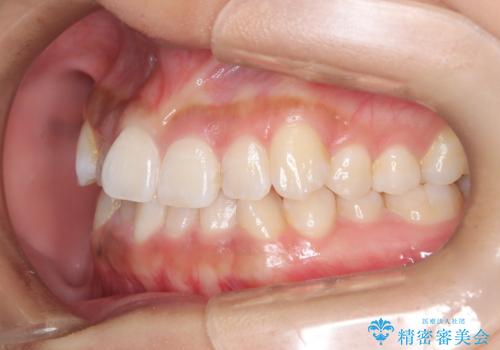

ワイヤー矯正で確実にガタつきを治したい セラミックブラケットによる治療

- 治療計画

- 前歯の叢生(がたつき)を主訴に来院された患者様です。以前マウスピース矯正をされていたそうでしたが、自身での継続が難しいことなどを理由に、ワイヤー矯正にて改めて矯正治療を希望されました。非抜歯にて治療を計画し治療を行いました。

歯の動きが良く、スムーズに治療を終了しました。一般的にワイヤー矯正はブラッシングが難しいのですが、毎回一生懸命セルフケアをされていたのが印象的です。治療においては、歯の衛生状態も一緒にチェック致します。